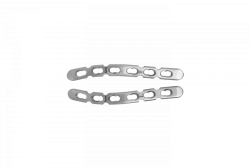

G-shaped Implant Plates, Left & Right, Article 475.53X R/L

US$9-36

Material:

Titanium alloy

Material:

Titanium alloy

OSTEOMED-M LLC 🇷🇺